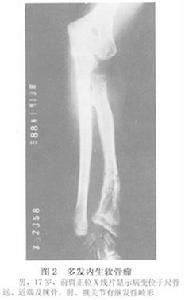

多發內生軟骨瘤病通常發病年齡為10歲以內患兒,男性多於女性。

症狀與體徵:表現為可觸及的腫塊,但很少有疼痛腫瘤侵及手或足,由於多發病變可以造成病殘。病變侵及長管狀骨,使內生軟骨骨化不能正常進行骨骺板不能正常生長因而肢體可以出現短縮彎曲畸形。如前臂向尺側彎曲畸形,下肢膝外翻等。當患者達到成年時腫瘤可停止生長。成人多發內生軟骨瘤病可發生惡性變,惡變率約為5%~25%。

X線檢查:多發內生軟骨瘤病的每一個病變的X線表現與單發內生軟骨瘤相似,但為多發。且有骨骼畸形或短縮。其乾骺端可以增寬。